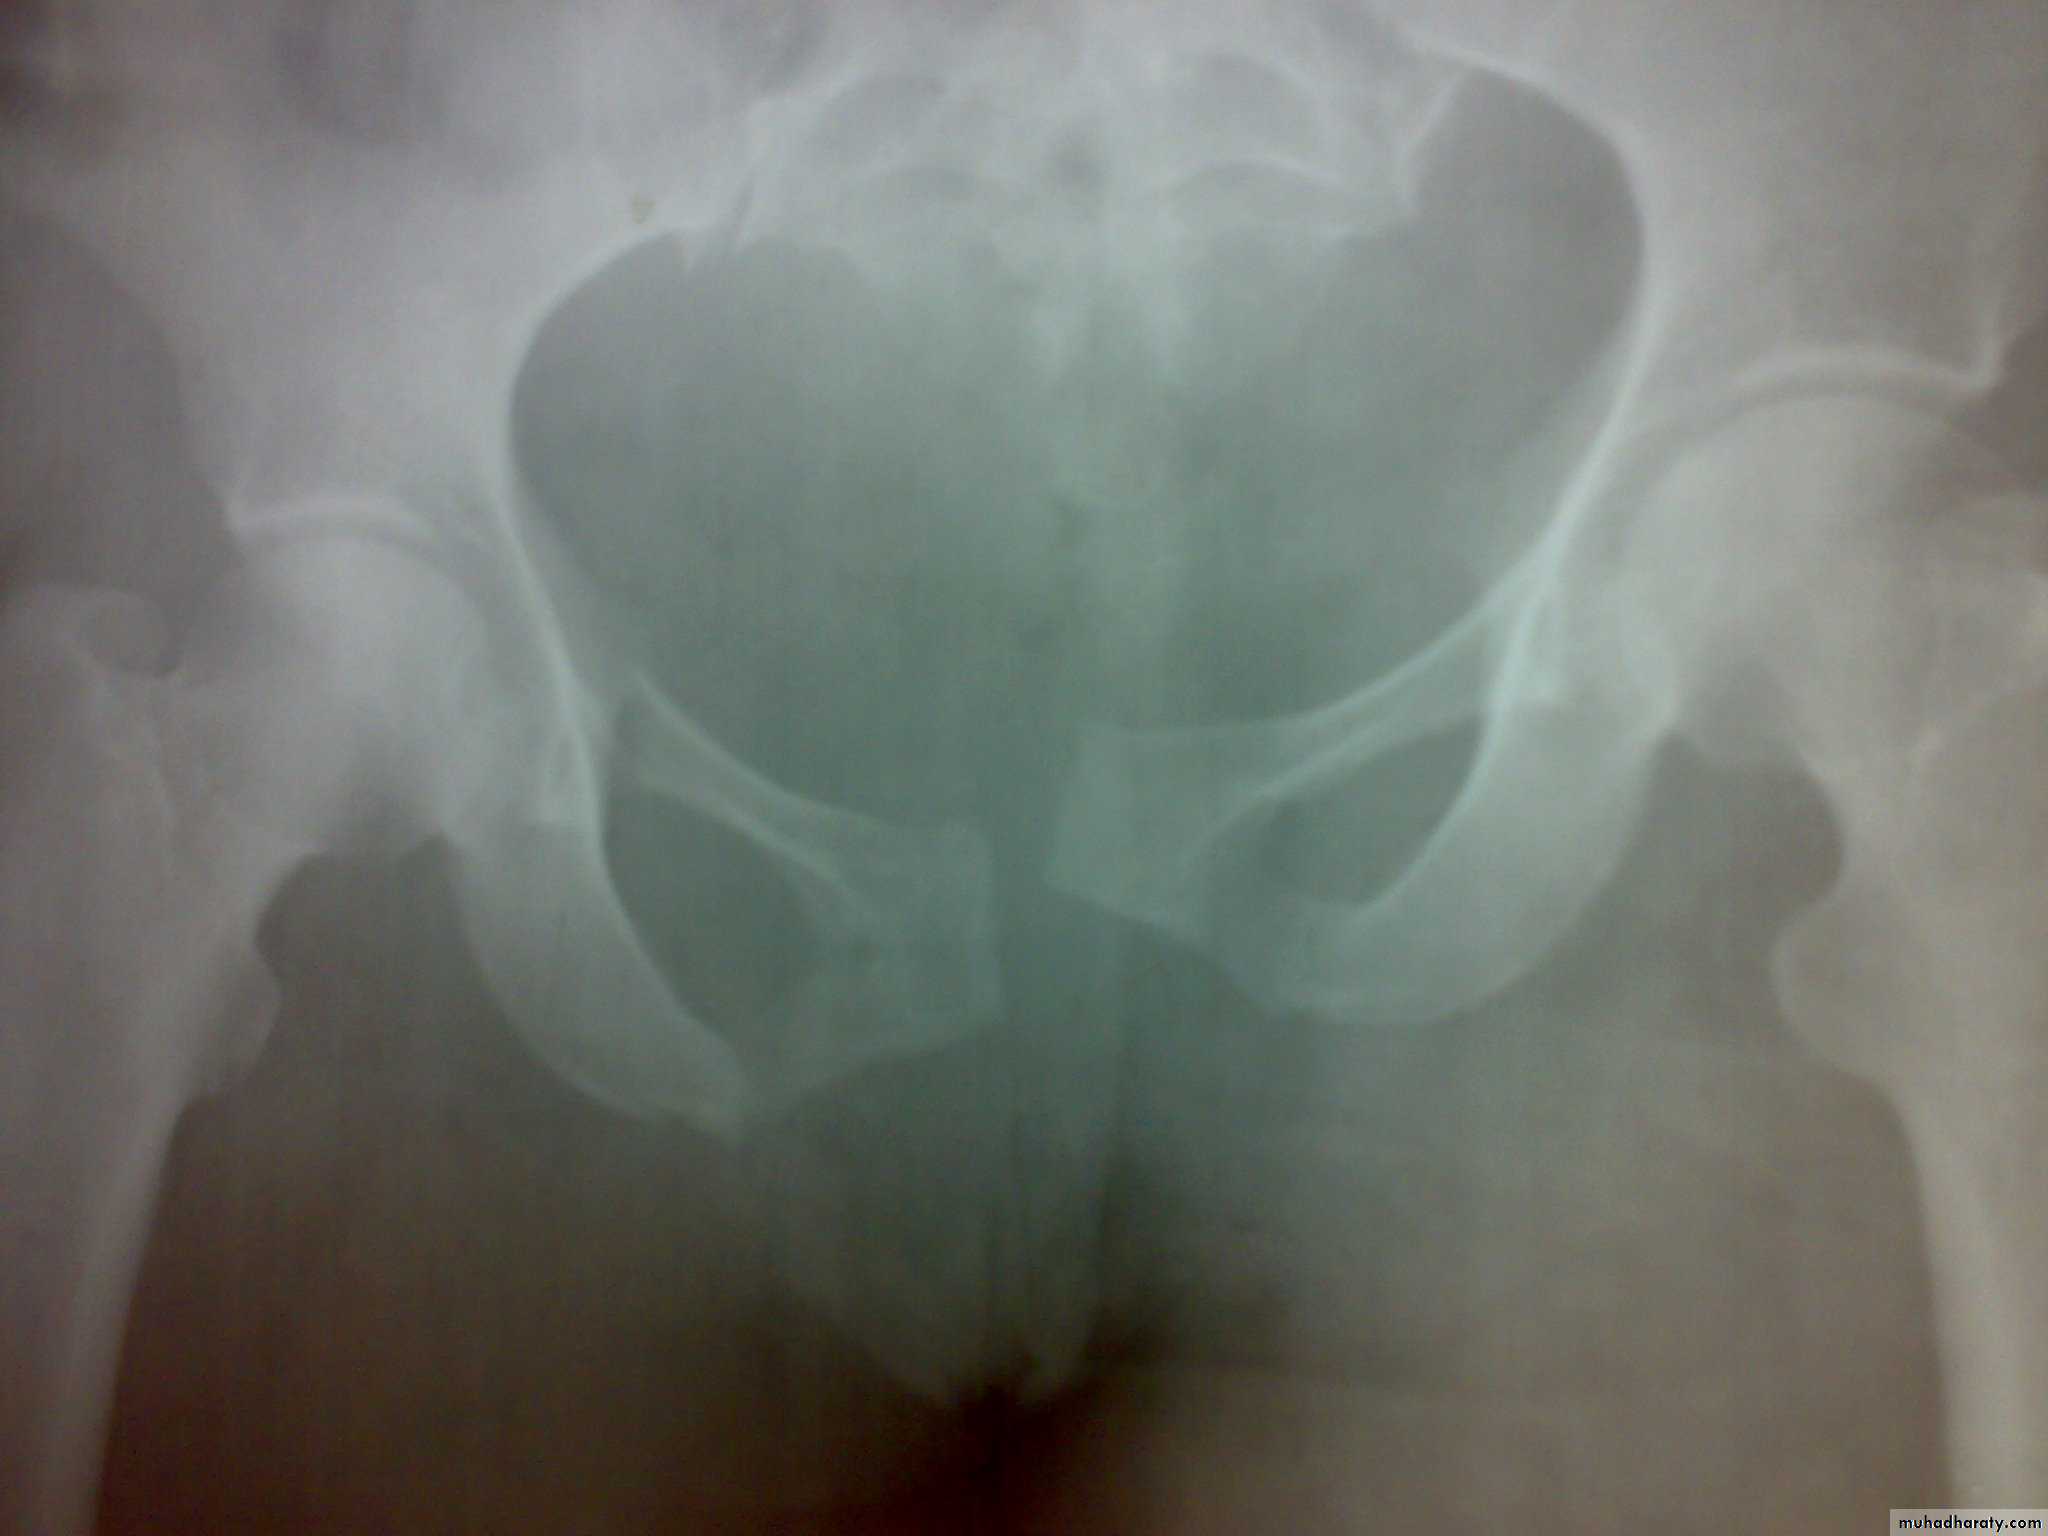

4- Sacrococcygeal fracture.

X- ray: Ideally five views should be obtained : Standard anteroposterior view, inlet view, outlet view, right oblique view, and left oblique view, but x-ray shouldn't be done until the patient become stable .